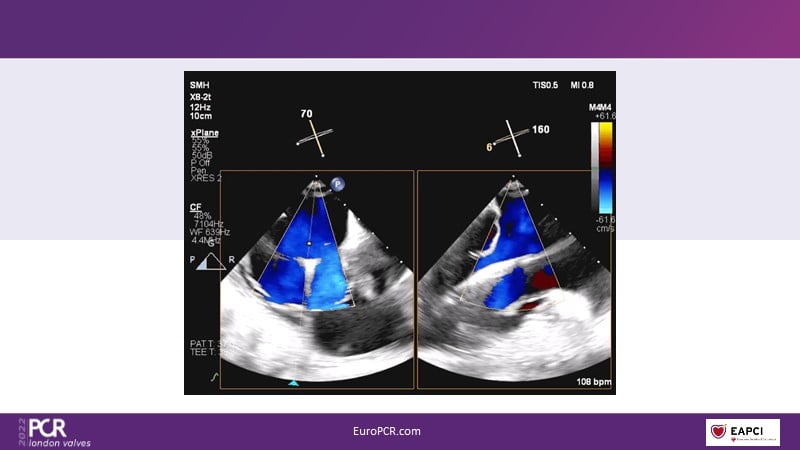

The right valves for the right ventricle: Venus MedTech tricuspid and pulmonary replacement systems

In this session from PCR London Valves 2022, discover the new Venus MedTech technology for tricuspid and pulmonary valve replacement, and a review of the clinical indications, selection criteria and procedural details.

- To learn about Venus MedTech technology, clinical indications and procedural details of valve replacement systems

- To learn more about the clinical experience and outcomes with Cardiovalve tricuspid and Venus P-valve